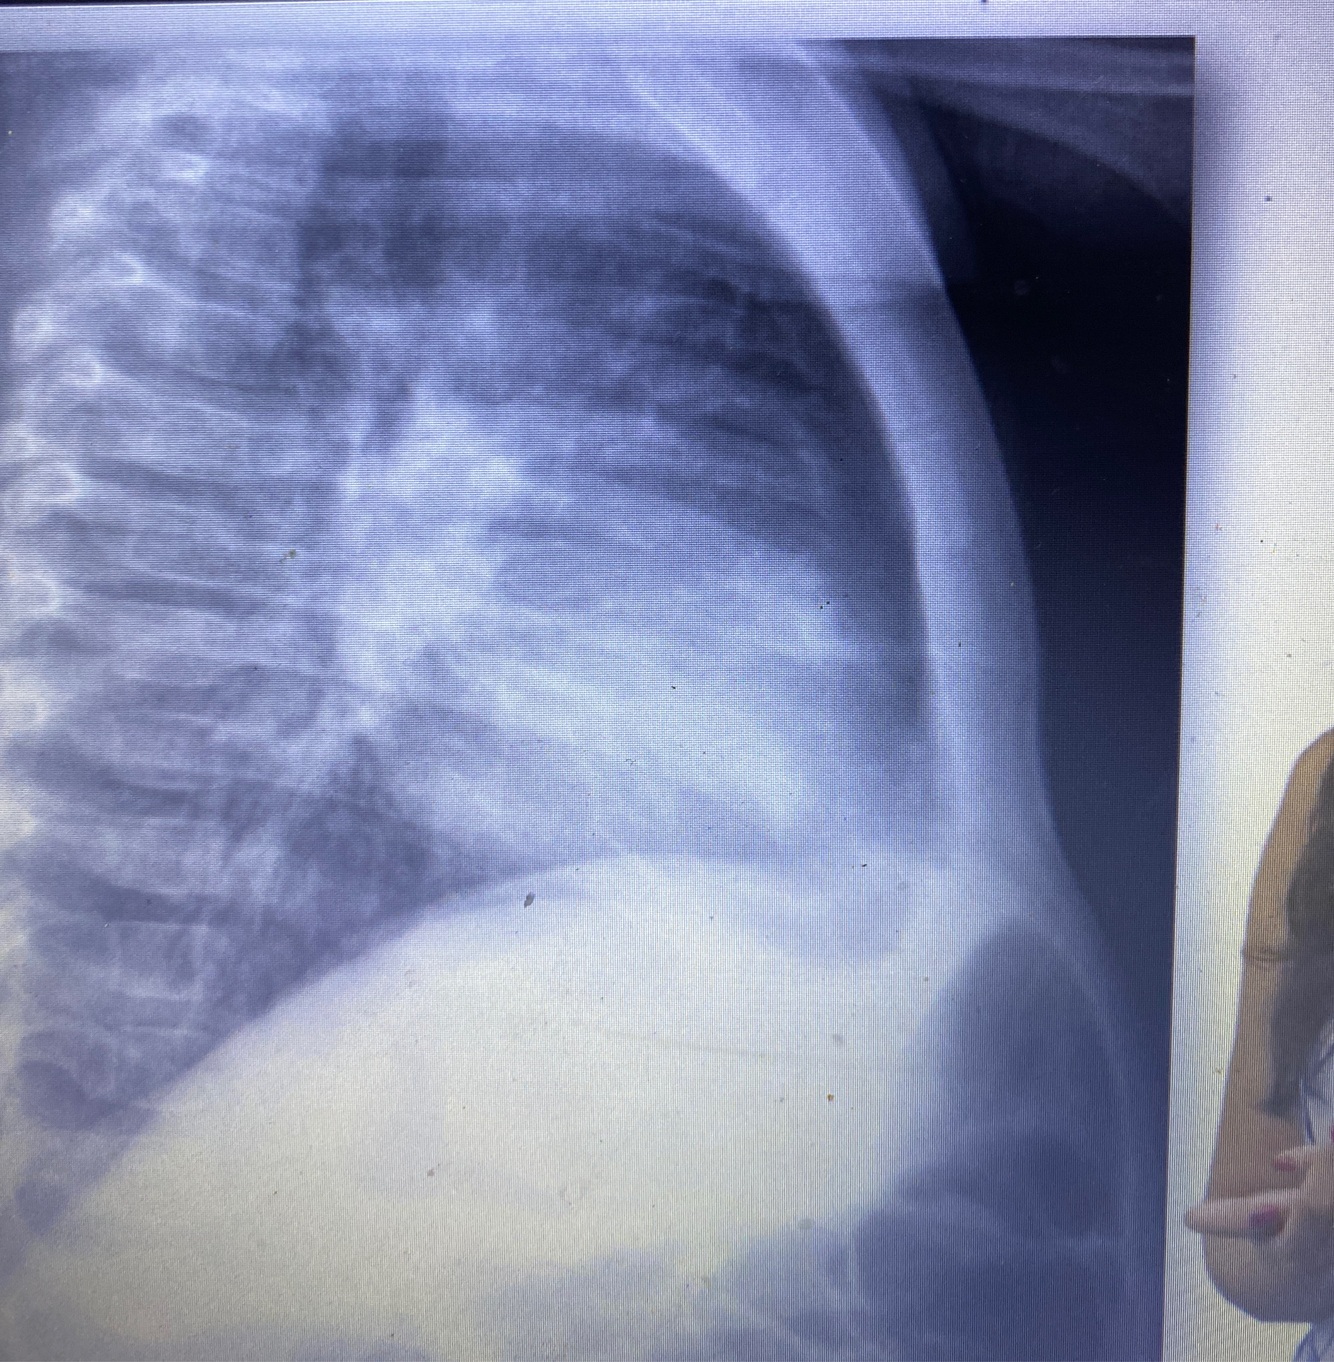

Rx de tórax

Pedir quando desconforto importante internação ver se tem atelectasia

Rx tórax oque ver

Hiperinsuflacao

Espessamento brônquico

Perfil: ar na frente do coração